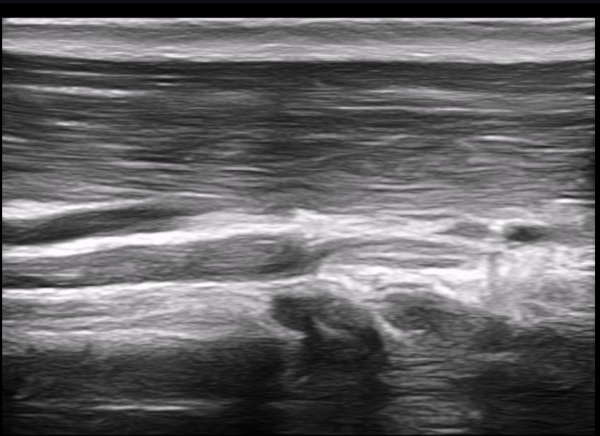

Å½ÃËÀÚ¸¦ Á¶±Ý ¸»´ÜÀ¸·Î À̵¿ÇÏ´Ï ±ÙÀ°ÇǺνŰæÀÇ À§ÃàÀÌ °üÂûµÇ°í(»çÁø 2) ŽÃËÀÚ¸¦ Á¶±Ý ´õ

¸»´ÜÀ¸·Î À̵¿ÇÏ´Ï ±ÙÀ°ÇǺνŰæÀÌ Á¤»êÀûÀ¸·Î °üÂûµÈ´Ù(»çÁø 3).

±ÙÀ°ÇǺνŰæÀÇ Á¾´Ü¸é°Ë»ç¿¡¼­ ±ÙÀ°ÇǺνŰæÀÇ ±¹¼ÒÀû ÇùÂø°ú ±ÙÀ§ºÎÀÇ Àú¿¡ÄÚ ºÎÁ¾ÀÌ °üÂûµÈ´Ù

(»çÁø 4, 5, 6,7) À̰ÍÀº ½Å°æÀÇ ¿°Àü(torsion)¿¡ ºÎÇÕÇÏ´Â ¼Ò°ßÀÌ´Ù.